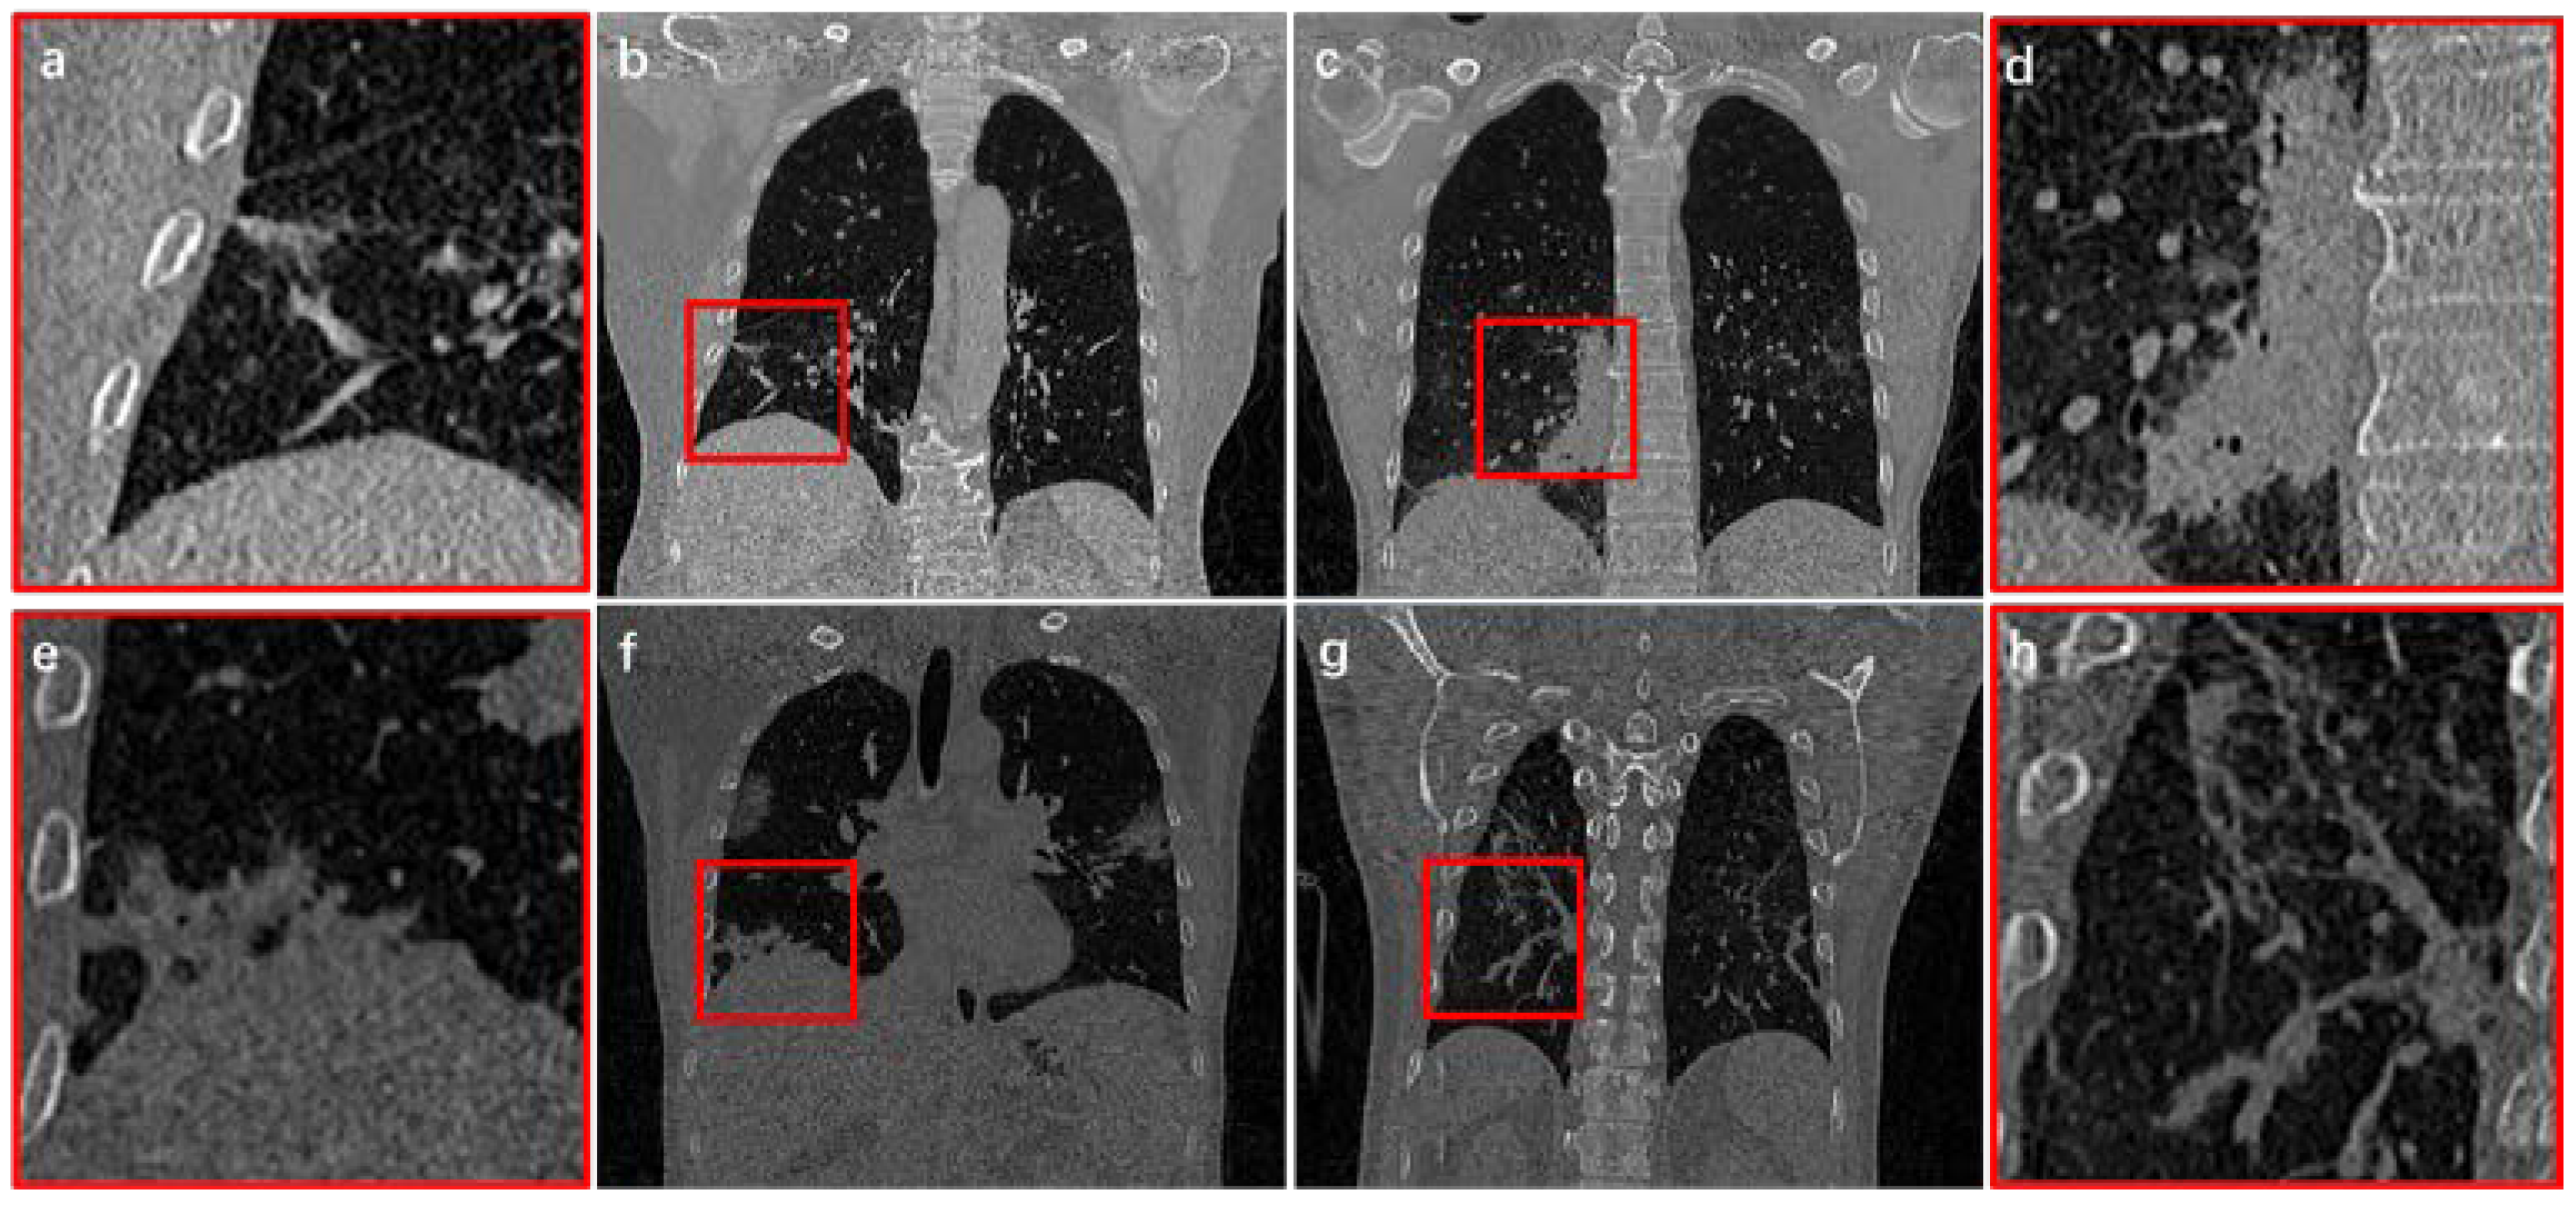

Since CT images can collect 3D information of patients, it is currently the most commonly clinical imaging technique for COVID-19 examination [15,16,17,18]. From CT images, COVID-19 infection present characteristics of regional spread, blurred boundaries, tissue adhesion, and large morphological differences (Figure 1). Therefore, identifying the method of how to extract infection effectively and accurately from COVID-19 CT images is a difficult and urgent challenge [19,20].

Figure 1.

Infection structure from COVID-19 CT images. (b,c,f,g) indicate four different cases. (a,d,e,h) are the local magnification structure of the red boxes from (b,c,f,g), respectively.

Although initial results have been achieved in reconstruction of COVID-19 infection, there are still some problems that still need to be solved: (1) When infections are adjacent to thorax, segmentation boundary cannot be effectively judged (Figure 1c); (2) Most methods focus on 2D images processing or partial patches, which cannot deal with complete 3D feature information in CT images; (3) COVID-19 infection usually only occupies a small part of the entire CT image. Thus, imbalance of positive and negative samples appears in network training, resulting in slow convergence and insufficient accuracy; (4) In vicinity of infected area, invasive structure of infection adheres to vessels and tracheas, which is difficult to distinguish effectively (Figure 1d).